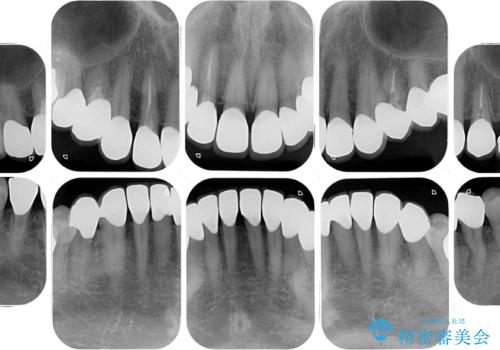

- 60歳を越え、黄ばんだ前歯をセラミッククラウンできれいな口元にしたいとのことで来院された患者様です。

診察したところ、前歯は反対咬合であり、その影響で抜歯が必要な奥歯があることが分かりました。

抜歯が必要な奥歯は、インプラント並びにブリッジにより補綴を行い、上下前歯は反対咬合を改善させるように補綴治療を行うこととしました。

健全な歯を削ってセラミッククラウンに置き換えることは、本来避けるべき治療と考えますが、今回は①患者様が60歳を越えていること、②要改善の咬合により抜歯が必要な奥歯があること、③反対咬合の前歯改善の手段としてセラミック治療が選択肢にあることなどから、全顎的なセラミック治療を行うこととしました。